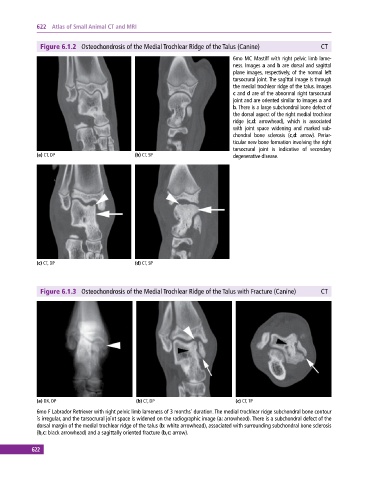

Figure 6.1.2 Osteochondrosis of the Medial Trochlear Ridge of the Talus (Canine) CT

6mo MC Mastiff with right pelvic limb lame

ness. Images a and b are dorsal and sagittal

plane images, respectively, of the normal left

tarsocrural joint. The sagittal image is through

the medial trochlear ridge of the talus. Images

c and d are of the abnormal right tarsocrural

joint and are oriented similar to images a and

b. There is a large subchondral bone defect of

the dorsal aspect of the right medial trochlear

ridge (c,d: arrowhead), which is associated

with joint space widening and marked sub

chondral bone sclerosis (c,d: arrow). Periar

ticular new bone formation involving the right

tarsocrural joint is indicative of secondary

(a) CT, DP (b) CT, SP degenerative disease.

(c) CT, DP (d) CT, SP

Figure 6.1.3 Osteochondrosis of the Medial Trochlear Ridge of the Talus with Fracture (Canine) CT

(a) DX, DP (b) CT, DP (c) CT, TP

6mo F Labrador Retriever with right pelvic limb lameness of 3 months’ duration. The medial trochlear ridge subchondral bone contour

is irregular, and the tarsocrural joint space is widened on the radiographic image (a: arrowhead). There is a subchondral defect of the

dorsal margin of the medial trochlear ridge of the talus (b: white arrowhead), associated with surrounding subchondral bone sclerosis

(b,c: black arrowhead) and a sagittally oriented fracture (b,c: arrow).